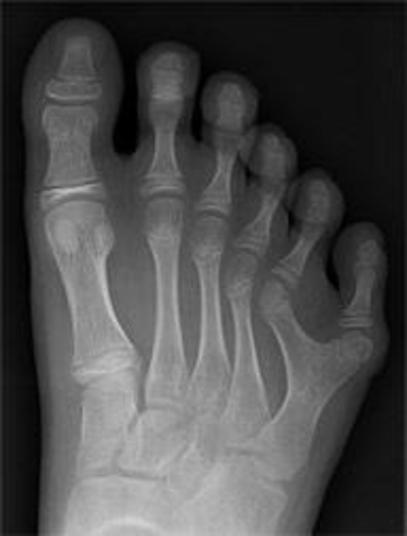

Um casal na China está pedindo ajuda no tratamento do seu filho, Hong Hong, de três meses, que nasceu com 15 dedos nas mãos e 16 dedos nos pés. As informações são do The Sun.

O objetivo é ter condições de realizar uma operação possível a partir dos seis meses, para que os dedos em excesso sejam retirados.

A mãe dele também tem uma anomalia, possuindo um dedo a mais em uma mão e em um dos pés. O pai da criança, Zou Chenglin, disse que eles temiam pela possibilidade de o filho ter esse problema.

Hong Hong e a mãe têm uma condição congênita chamada polidactilia, uma anomalia causada porque uma formação alternativa do gene (alelo) é dominante nessa situação.

O problema em si não gera riscos à saúde ou à vida, mas o estigma causado pela anomalia pode gerar traumas e atrapalhar no dia-a-dia da pessoa

O problema em si não gera riscos à saúde ou à vida, mas o estigma causado pela anomalia pode gerar traumas e atrapalhar no dia-a-dia da pessoa.